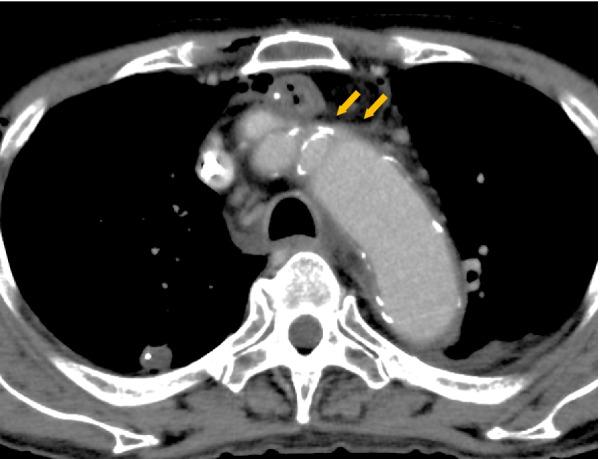

This study included 66 patients who underwent esophagectomy with retrosternal reconstruction using a gastric tube. All patients routinely underwent contrast-enhanced computed tomography (CT) on the 4th postoperative day. Low-molecular-weight-heparin (LMWH) was routinely administered by the 2nd postoperative day. To evaluate retrosternal space's width, (a) The distance from sternum to brachiocephalic artery and (b) the distance from sternum to vertebra were measured by preoperative CT, and the ratio of (a) to (b) was defined as the width of retrosternal space.

RESULTS

Among all patients, 11 (16.7%) suffered from UEDVT, and none was preoperatively received CVC placement, while 7 were inserted in non-UEDVT cases. Retrosternal space's width in patients with UEDVT was significantly smaller than that in patients without UEDVT (0.17 vs. 0.26; P < 0.0001). A cutoff value of the width was 0.21, which has high sensitivity (87%) and specificity (82%) for UEDVT prediction, respectively.

本研究纳入了 66 例行胸骨后胃管重建的食管癌切除术患者。所有患者术后第 4 天常规行增强 CT 检查。术后第 2 天常规给予低分子肝素(LMWH)。为评估胸骨后空间的宽度,(a)术前 CT 测量胸骨至头臂动脉的距离,(b)胸骨至椎体的距离,并定义(a)与(b)的比值为胸骨后空间的宽度。

结果

所有患者中,有 11 例(16.7%)发生 UEDVT,无一例术前接受 CVC 放置,而非 UEDVT 患者中有 7 例接受 CVC 放置。UEDVT 患者胸骨后空间的宽度明显小于非 UEDVT 患者(0.17 比 0.26;P < 0.0001)。宽度的截断值为 0.21,对 UEDVT 的预测具有较高的敏感性(87%)和特异性(82%)。